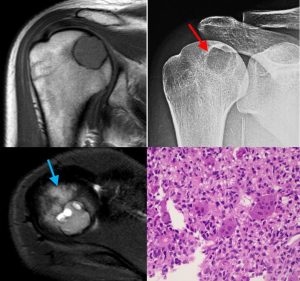

One such is the concept of the “benign aggressive” lesion. Clinically, these are defined as benign tumors with locally aggressive behavior. Radiologically, these are defined as tumors that appear benign on X-rays but aggressive on MRI with marrow and perosseous edema, effusion and periosteal reaction, but without a soft tissue mass.

- Osteoid osteoma / Osteoblastoma (Fig. 1)